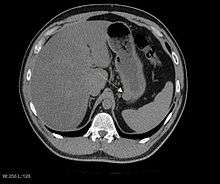

CT scanning is often undertaken (see the radiology section).

The purpose of radiologic imaging is to locate the lesion, evaluate for signs of invasion and detect metastasis. Features of GIST vary depending on tumor size and organ of origin. The diameter can range from a few millimeters to more than 30 cm. Larger tumors usually cause symptoms in contrast to those found incidentally which tend to be smaller and have better prognosis.[3][15] Large tumors tend to exhibit malignant behavior but small GISTs may also demonstrate clinically aggressive behavior.[16]

Since GISTs arise from the bowel layer called muscularis propria (which is deeper to the mucosa and submucosa from a luminal perspective), small GIST imaging usually suggest a submucosal process or a mass within the bowel wall. In barium swallow studies, these GIST most commonly present with smooth borders forming right or obtuse angles with the nearby bowel wall, as seen with any other intramural mass. The mucosal surface is usually intact except for areas of ulceration, which are generally present in 50% of GISTs. Ulcerations fill with barium causing a bull's eye or target lesion appearance. In contrast-enhanced CT, small GISTs are seen as smooth, sharply defined intramural masses with homogeneous attenuation.

Large GISTs

As the tumor grows it may project outside the bowel (exophytic growth) and/or inside the bowel (intraluminal growth), but they most commonly grow exophytically such that the bulk of the tumor projects into the abdominal cavity. If the tumor outstrips its blood supply, it can necrose internally, creating a central fluid-filled cavity with hemorrhage and cavitations that can eventually ulcerate and communicate into the lumen of the bowel. In that case, barium swallow may show an air, air-fluid levels or oral contrast media accumulation within these areas.[16][17] Mucosal ulcerations may also be present. In contrast enhanced CT images, large GISTs appear as heterogeneous masses due to areas of living tumor cells surrounding hemorrhage, necrosis or cysts, which is radiographically seen as a peripheral enhancement pattern with a low attenuation center.[15] In MRI studies, the degree of necrosis and hemorrhage affects the signal intensity pattern. Areas of hemorrhage within the tumor will vary its signal intensity depending on how long ago the hemorrhage occurred. The solid portions of the tumor are typically low signal intensity on T1-weighted images, are high signal intensity on T2-weighted images and enhance after administration of gadolinium. Signal-intensity voids are present if there is gas within areas of necrotic tumor.[18][19][20]

Features of malignancy

Malignancy is characterized by local invasion and metastases, usually to the liver, omentum and peritoneum. However, cases of metastases to bone, pleura, lungs and retroperitoneum have been seen. In distinction to gastric adenocarcinoma or gastric/small bowel lymphoma, malignant lymphadenopathy (swollen lymph nodes) is uncommon (<10%) and thus imaging usually shows absence of lymph node enlargement.[15] If metastases are not present, other radiologic features suggesting malignancy include: size (>5 cm), heterogeneous enhancement after contrast administration and ulcerations.[3][15][21] Also, overtly malignant behavior (in distinction to malignant potential of lesser degree) is less commonly seen in gastric tumors, with a ratio of behaviorally benign to overtly malignant of 3-5:1.[3] Even if radiographic malignant features are present, these findings may also represent other tumors and definitive diagnosis must be made immunochemically.

Imaging

Plain radiographs are not very helpful in the evaluation of GISTs. If an abnormality is seen, it will be an indirect sign due to the tumor mass effect on adjacent organs. On abdominal x-ray, stomach GISTs may appear as a radiopaque mass altering the shape of the gastric air shadow. Intestinal GISTs may displace loops of bowel and larger tumors may obstruct the bowel and films will show an obstructive pattern. If cavitations are present, plain radiographs will show collections of air within the tumor.[18] Calcification is an unusual feature of GIST but if present can be visible on plain films.

Barium fluoroscopic examinations and CT are commonly used to evaluate the patient with abdominal complaints. Barium swallow images show abnormalities in 80% of GIST cases.[16] However, some GISTs may be located entirely outside the lumen of the bowel and will not be appreciated with a barium swallow. Even in cases when the barium swallow is abnormal, an MRI or CT scan must follow since it is impossible to evaluate abdominal cavities and other abdominal organs with a barium swallow alone. In a CT scan, abnormalities may be seen in 87% of patients and it should be made with both oral and intravenous contrast.[16] Among imaging studies, MRI has the best tissue contrast, which aids in the identification of masses within the GI tract (intramural masses). Intravenous contrast material is needed to evaluate lesion vascularity.

Preferred imaging modalities in the evaluation of GISTs are CT and MRI,[22]:20–21 and, in selected situations, endoscopic ultrasound. CT advantages include its ability to demonstrate evidence of nearby organ invasion, ascites and metastases. The ability of MRI to produce images in multiple planes is helpful in determining the bowel as the organ of origin (which is difficult when the tumor is very large), facilitating diagnosis.